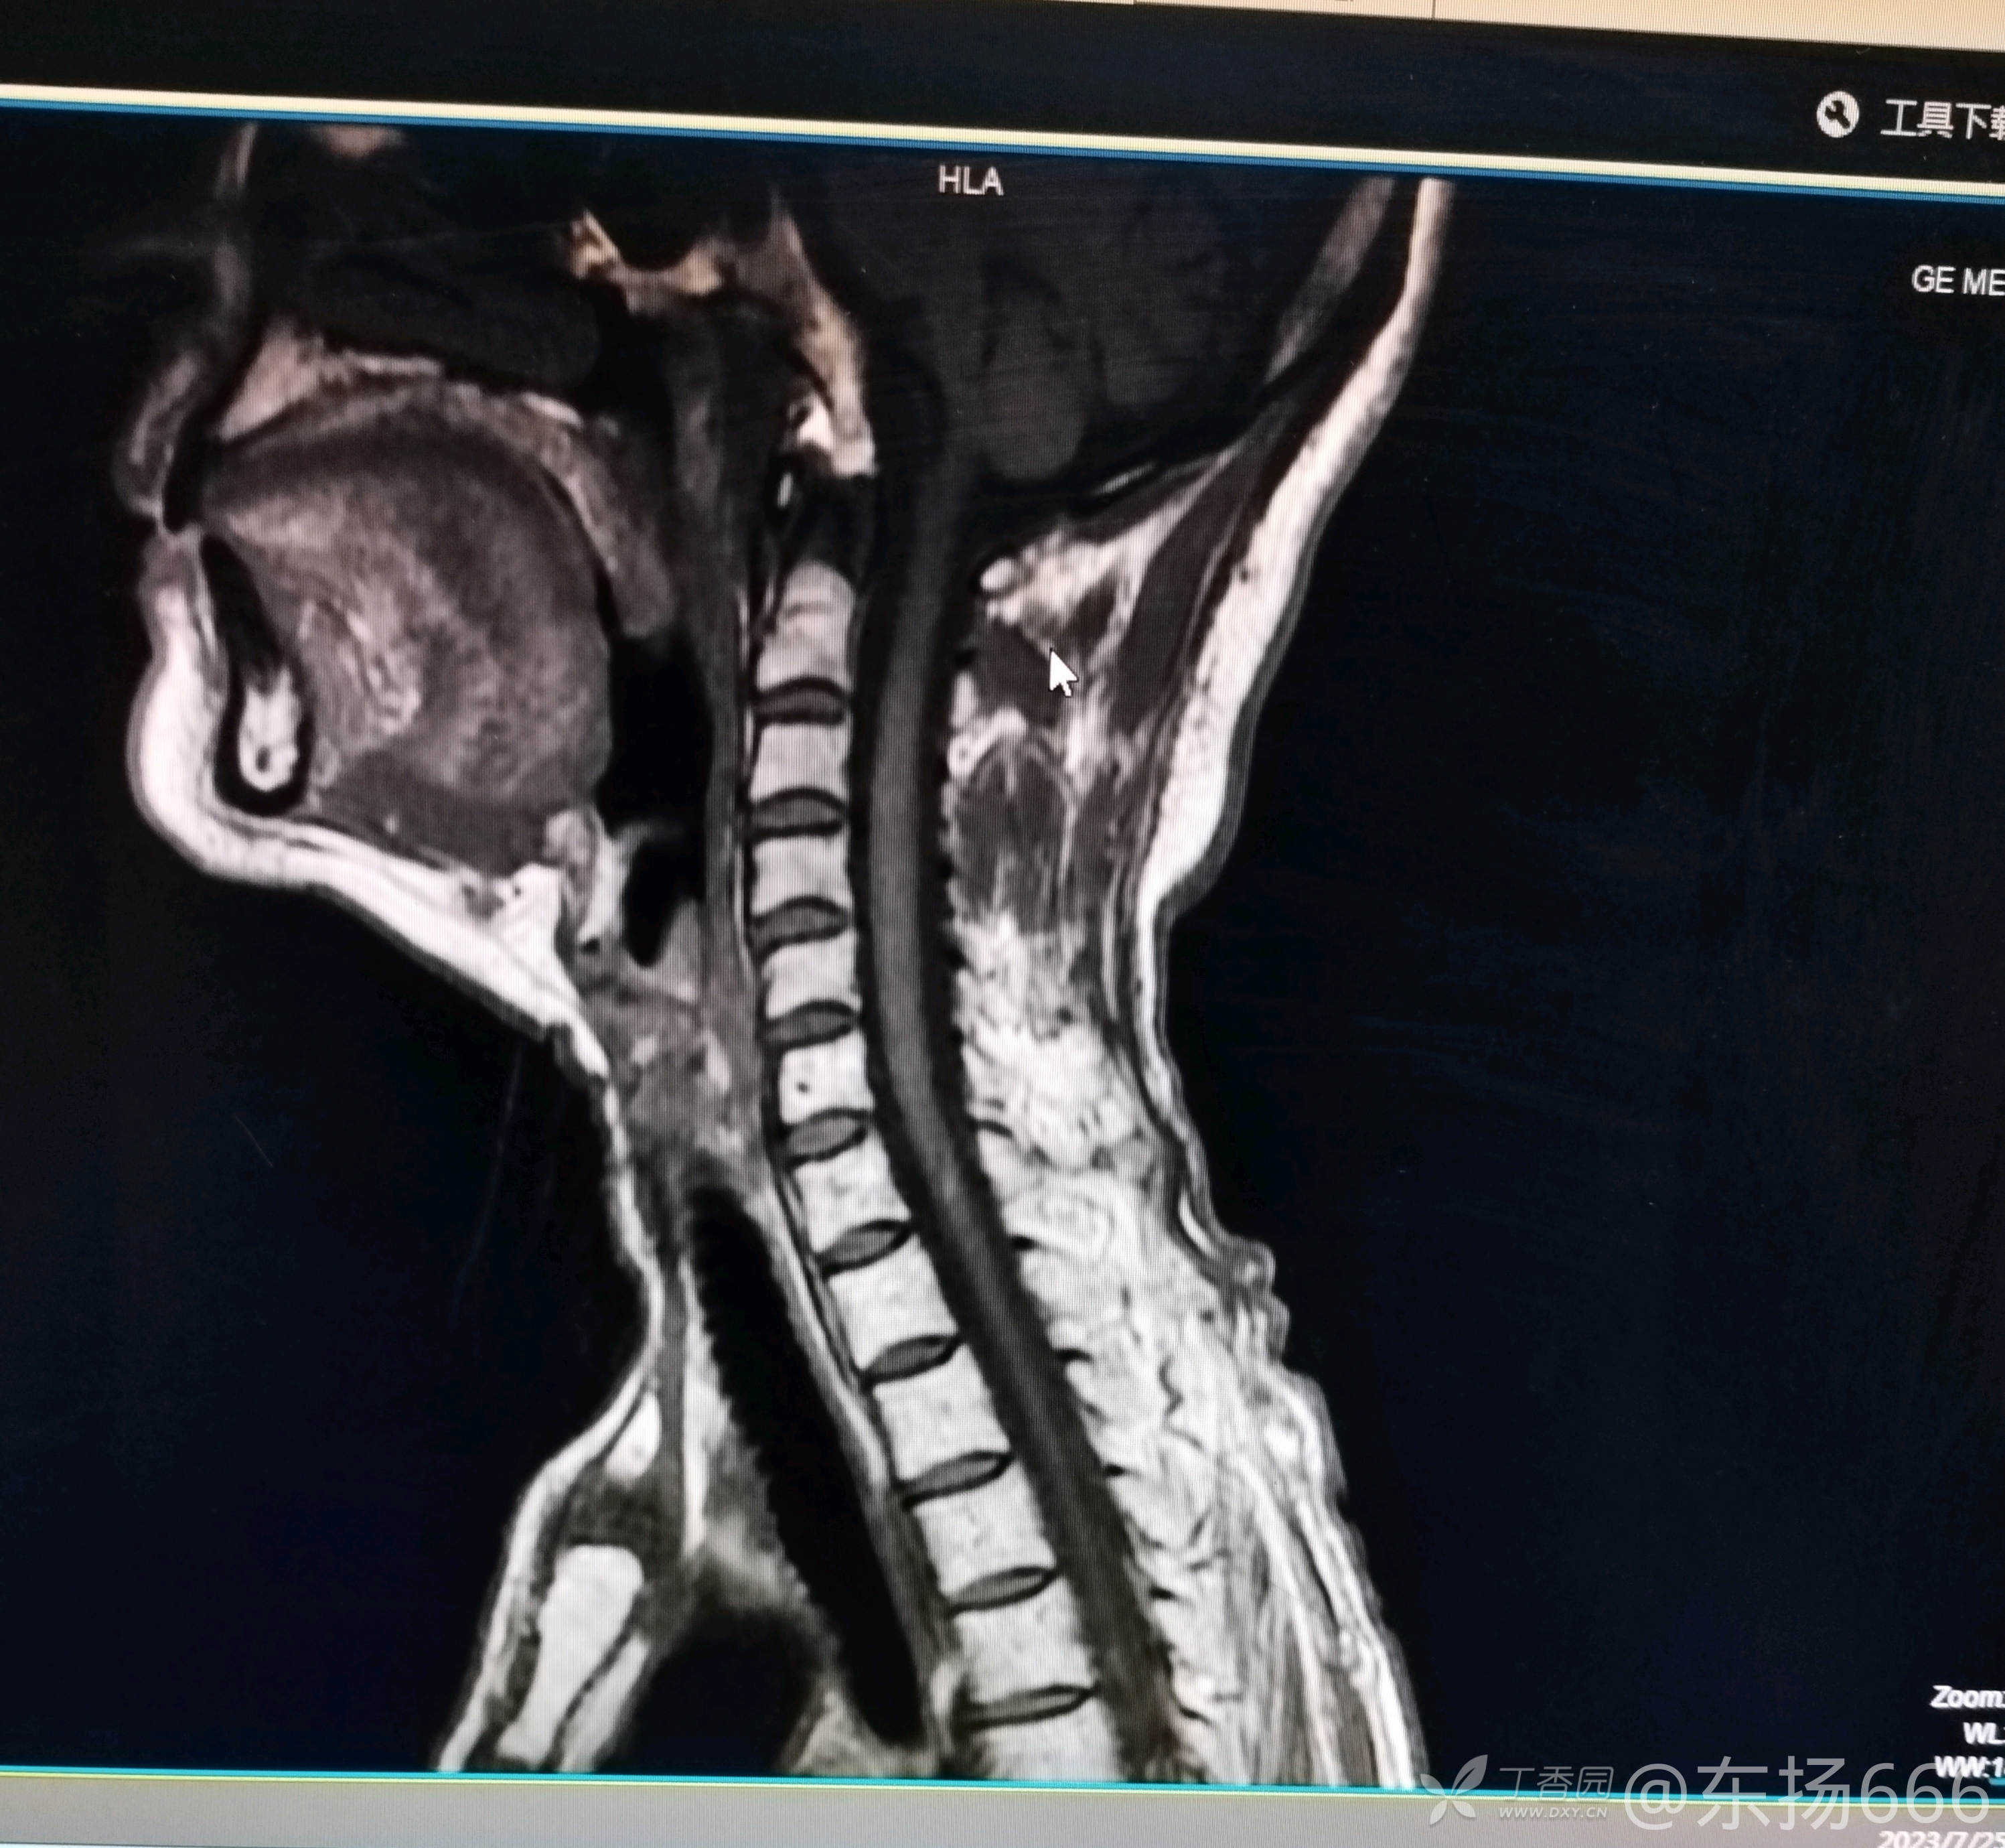

我院行颈椎MR示:颈椎间盘退行性病变。C2-7椎间盘突出